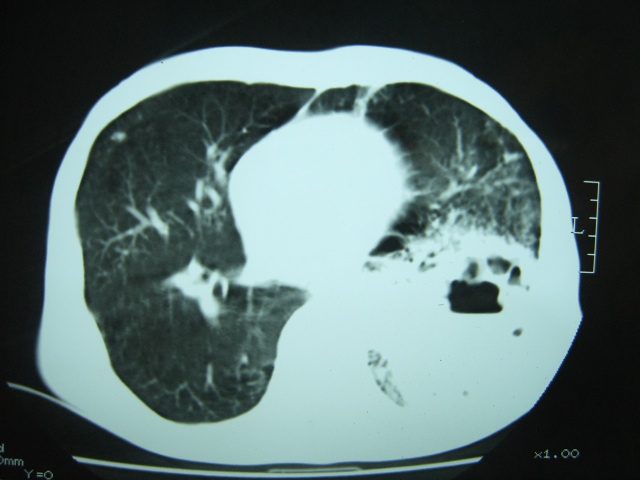

男74岁,咳嗽,寒战,低烧。有糖尿病史。

两肺慢性炎症伴脓肿形成,不除外继发霉菌感染。

两肺结核,左下肺空洞性病变,结核性?炎性?癌性?抗炎治疗后复查。

两肺结核,左下肺大片实变,内见空洞性病变,壁不规则,结合糖尿病史,考虑:结核性?霉菌性?建议结合实验室检查或治疗后复查。